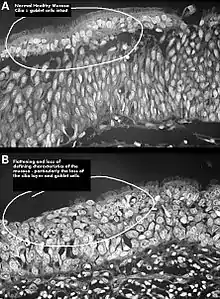

لا توجد نتائج فحص بدني موضوعية تشخص متلازمة الأنف الفارغة بصورة أكيدة،[1] فقد ينقص أو يغيب واحد أو أكثر من المحارات عند مشاهدتها في التصوير الطبي أو من خلال المنظار الداخلي دون أي علامة على وجود انسداد أنفي، ويكون الغشاء المخاطي جافًا وباهتًا، وقد تكون هناك علامات على عدوى ثانوية.[1]